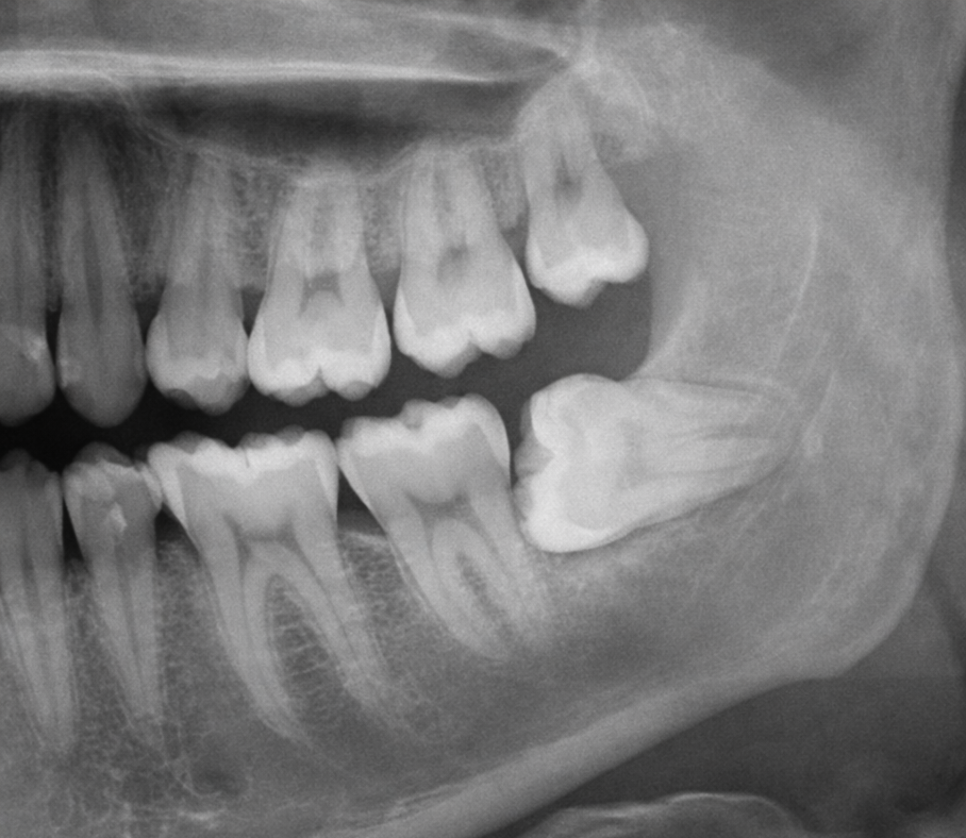

안녕하세요, 마곡동 치과 통합치의학 전문의 이수경입니다. "사랑니 뽑고 3일 됐는데 통증이 점점 더 심해져요" "뼈가 보이는 것 같고 냄새도 나요. 괜찮은 건가요?" . . . 사랑니 발치 후 이런 증상을 경험하셨다면 드라이소켓(dry socket)을 의심해 볼 수 있습니다. https://pmc.ncbi.nlm....

사랑니 발치 후

이런 증상을 경험하셨다면

드라이소켓(dry socket)을

의심해 볼 수 있습니다.

의학용어로 '건성발치와'라고 부르며

발치 후 생긴 구멍에

혈병(피딱지)이 형성되지 않거나

떨어져 나가면서 발생합니다.

사랑니를 뽑으면 그 자리에 피가 고여

'혈병'(blood clot)이 만들어지는데

이 혈병은 상처를 보호하고

새로운 조직이 자라나도록 돕는

중요한 역할을 합니다.

마치 무릎을 다쳤을 때 생기는 딱지처럼

발치 부위를 보호하는 자연스러운

치유 과정인 것이죠.

그런데 이 혈병이

너무 일찍 떨어져 나가면

뼈와 신경이 그대로 노출되어

극심한 통증이 발생합니다.

일반적으로 발치 후

2~4일 사이에 가장

많이 나타나며

특히 아래(하악) 사랑니를

뽑았을 때 발생률이 높습니다.